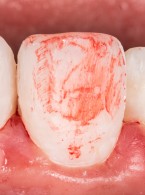

REPORTAŻ KLINICZNY. Bezpośrednia biomimetyczna odbudowa kompozytem zębów siecznych po urazie

Dawid Pisuk